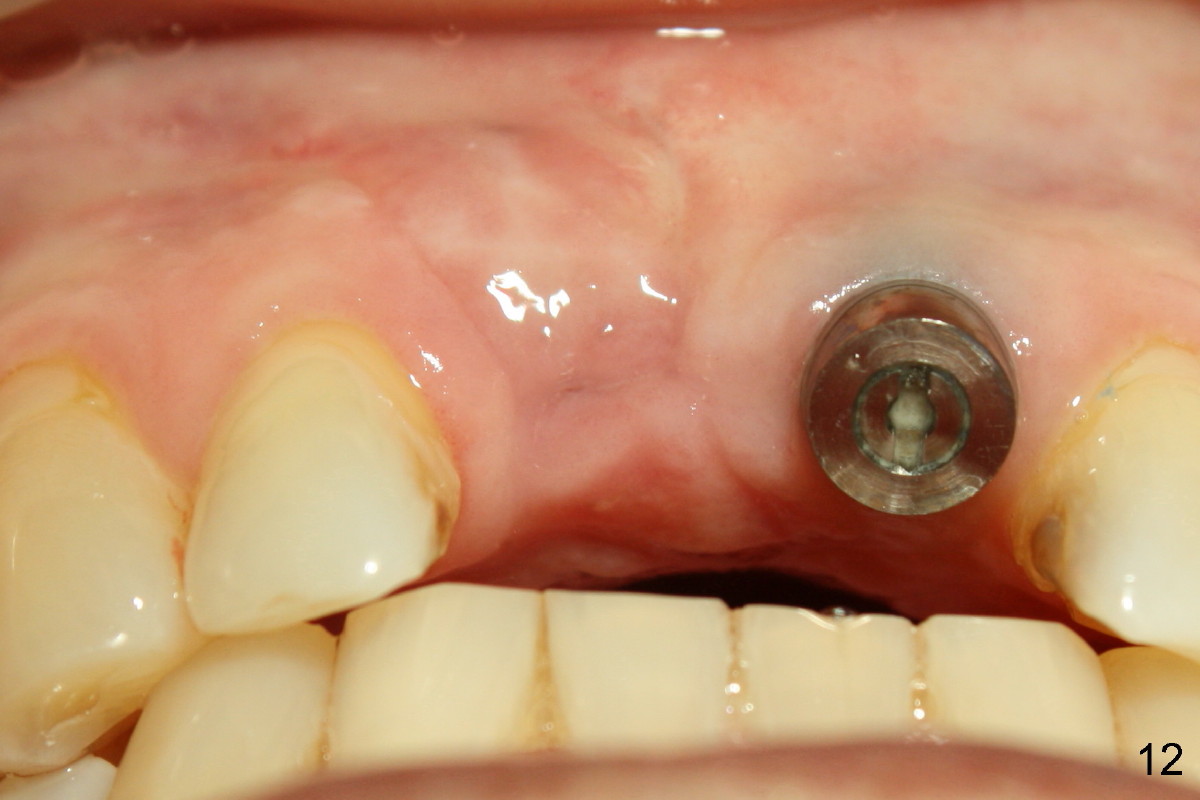

Update: Fig.12 is taken 15 days after implant removal.